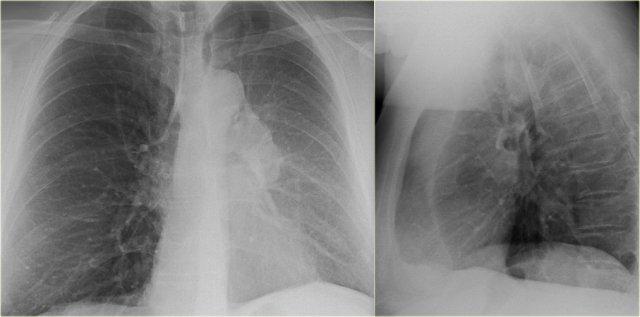

Xẹp thùy giữa phổi phải

Hãy quan sát kỹ các hình X-quang trước, sau đó tiếp tục đọc.

Các dấu hiệu là gì?

- Xóa mờ bờ tim phải (dấu hiệu bóng mờ)

- Đám mờ hình tam giác trên phim nghiêng do xẹp thùy giữa

Thông thường, xẹp thùy giữa phổi phải không gây nâng cao cơ hoành phải đáng kể.

Ngực lõm (pectus excavatum) có thể bắt chước hình ảnh xẹp thùy giữa trên phim thẳng, nhưng phim nghiêng sẽ giúp phân biệt được vấn đề này.